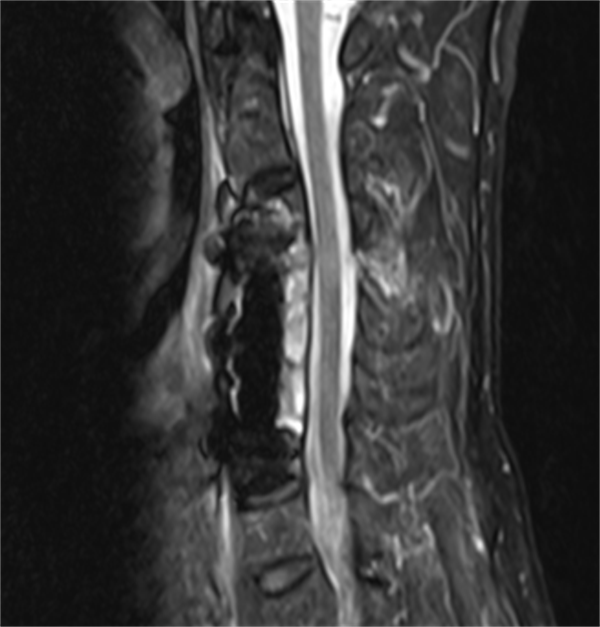

患者完善术前准备后,手术由刘辉主任医师主刀、熊志鹏副主任协助。术中全麻后颈椎脱位经手法复位完全纠正,前路椎体次全切除后脊髓减压充分,融合器及内固定装置植入标准,颈椎稳定性恢复可靠。手术用时仅1小时,出血仅50毫升,组织损伤小,手术顺利完成!

术后在进行常规治疗的同时结合快速康复理念,邀请康复医学科早期介入,为刘伯制定“一对一”的功能康复方案。术后第3天刘伯就可下床步行活动,经过近10天专业的综合治疗后,刘伯四肢肌力基本恢复正常,双手活动良好。出院时刘伯开心的说道:“感谢脊柱外科全体医护,正是因为有你们这样医术精湛的骨科专家,有二医院这样为民服务的公立医院,我才能重获正常生活!”

术后